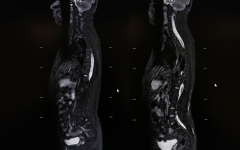

早高峰车祸重伤 西安国际医学中心医院多学科接力上演生死时速